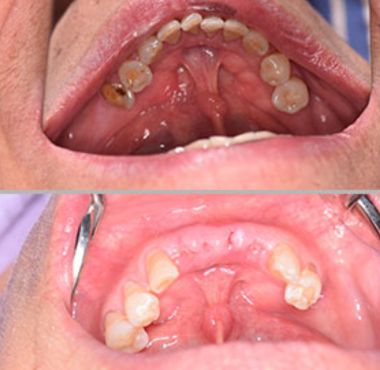

- Mantenedor de espacio

Es un dispositivo que se coloca cuando se ha perdido un diente de leche de manera temprana, este se encarga de mantener el espacio para que el diente definitivo pueda erupcionar sin inconvenientes.